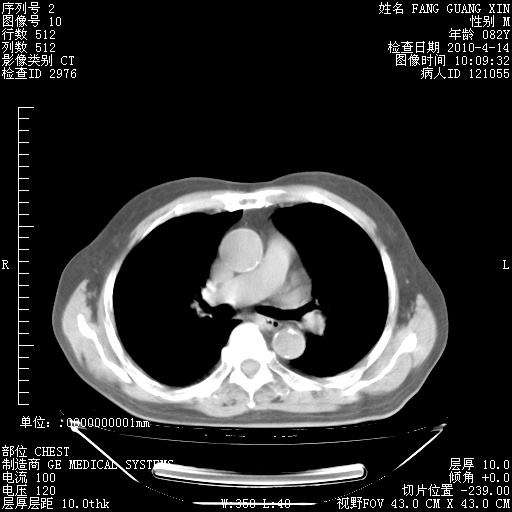

4月14日肺部CT

肺部CT平扫未见异常。